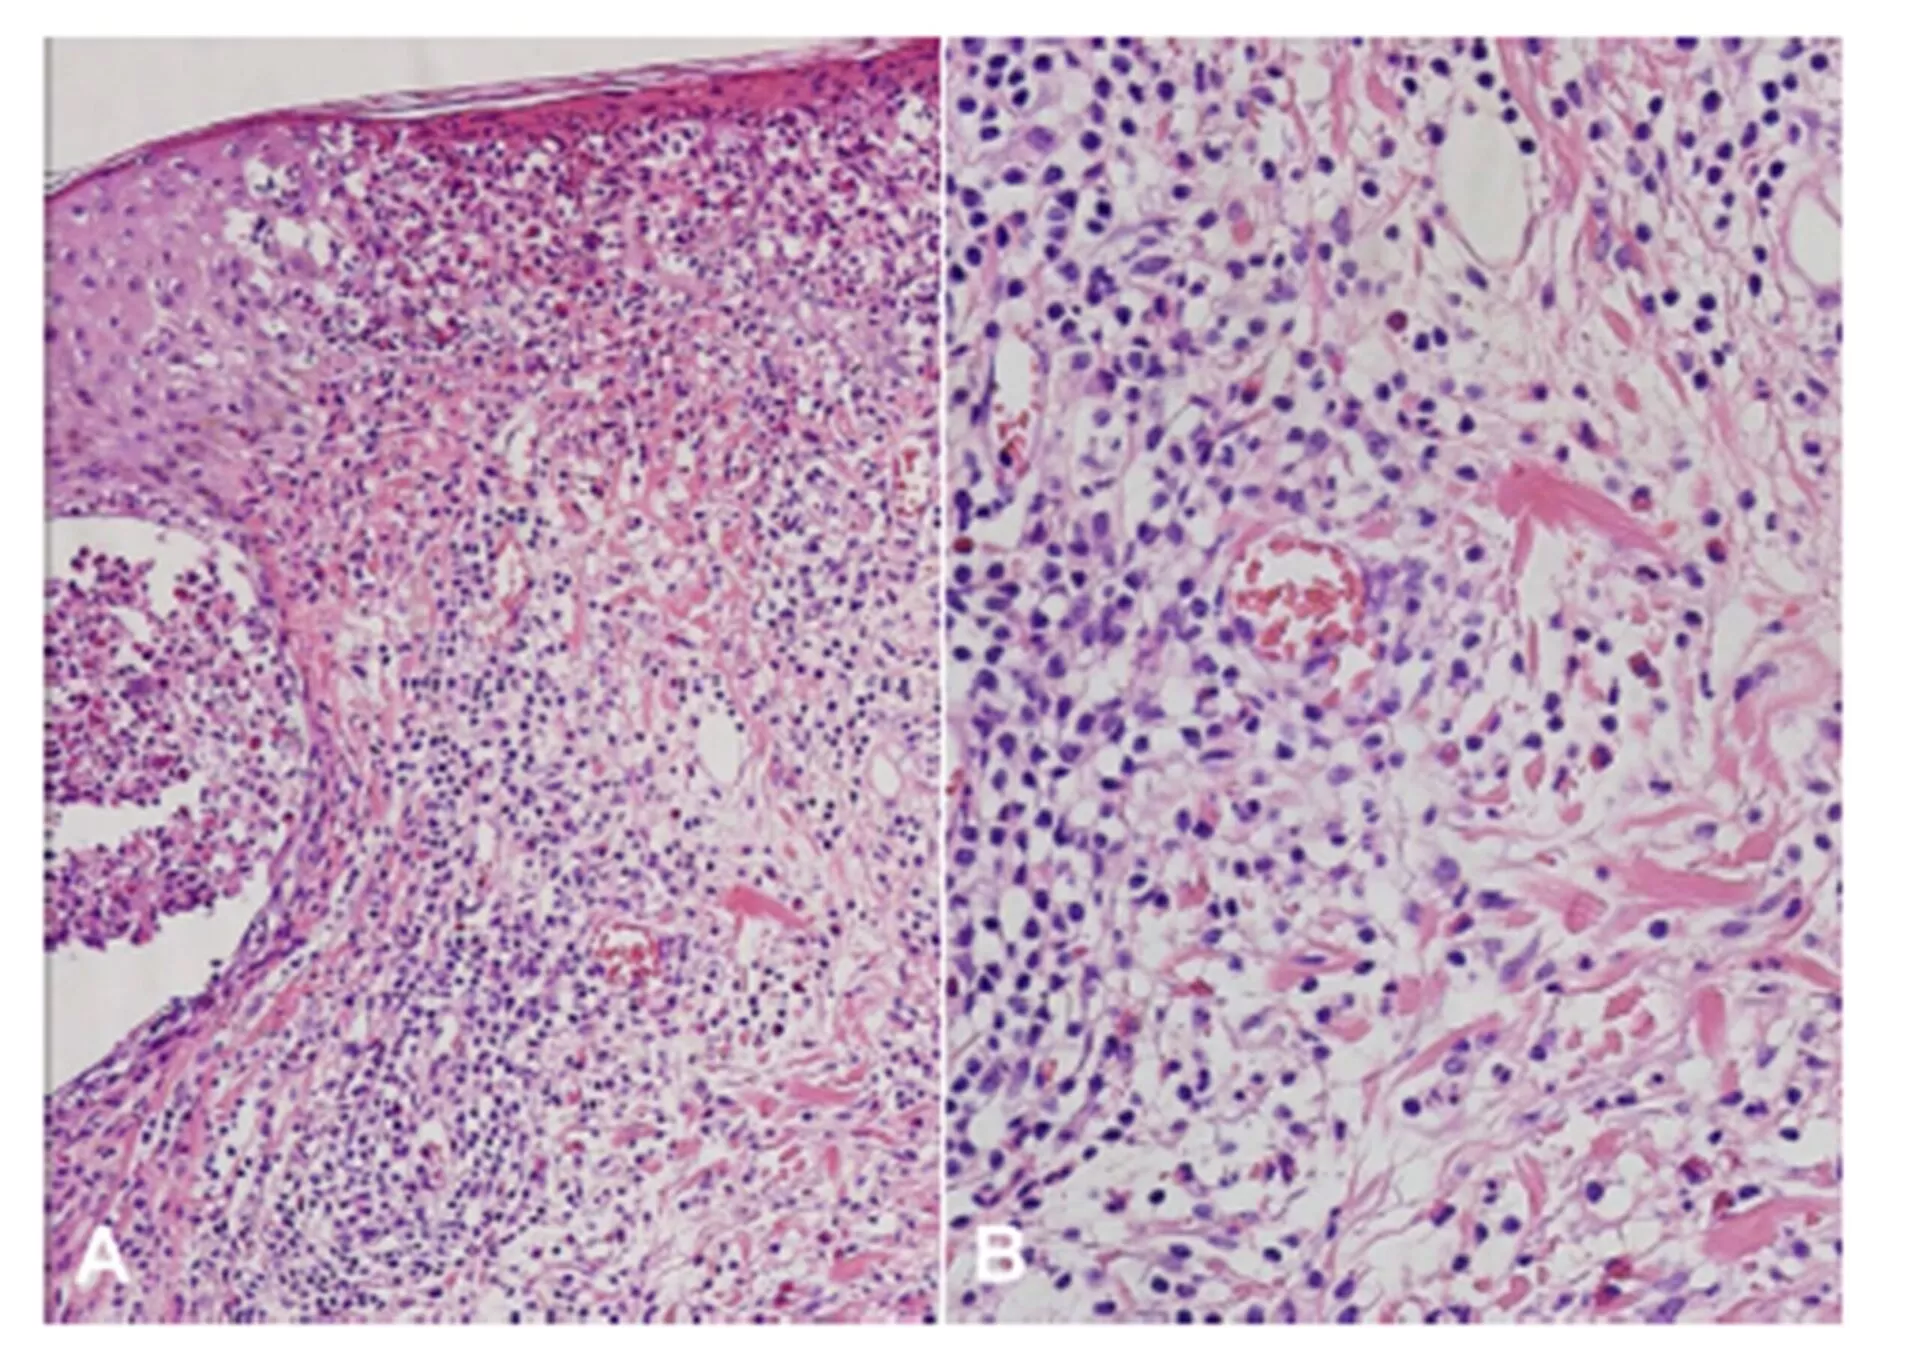

Specimens obtained from the patient’s facial skin lesions showed marked infiltration of eosinophils into the epidermis, hair follicles, and perifollicular areas. There was also lymphocytic infiltration in the dermis near the vessels (Figure 2). Direct immunofluorescence studies of the biopsy specimens were negative. The patient was diagnosed with BD based on the guidelines of the International Study Group for BD with diagnostic criteria of recurrent oral ulceration, genital ulceration and positive pathergy reaction (6). She was also diagnosed with EPF based on the histopathology and clinical manifestations (7). The patient showed clinical improvements in the vesicopustular skin lesions with the systemic administration of cyclosporine and topical 0.1% tacrolimus ointment (Protopic®; Astellas Toyama Co., Ltd., Toyama, Japan).

A) Marked infiltration of eosinophils into hair follicles and perifollicular areas with (B) dermal lymphocytic infiltration around the blood vessels(H&E, A: X200, B: X400)

Figure 2: (A) Marked infiltration of eosinophils into hair follicles and perifollicular areas with (B) dermal lymphocytic infiltration around the blood vessels (H&E, A: X200, B: X400)

The patient in this case presented with histopathologic features that are both suggestive of EPF and skin manifestations in BD. Numerous eosinophils were gathered around the follicles and lymphohistiocyte infiltration around the vessels were noted.